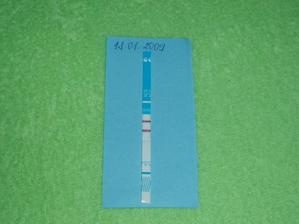

16.01.2009 som si robila prvý tehotenský testík vyšiel pozitívne 🙂 pre istotu som robila ďalší testík 18.01.2009 a čiaročka bola ešte silnejšia.Týždeň sme boli v nemocnici, kvôli komplikáciam, ale našťastie sme to s naším malým krtkom zvládli. Od 19.04. (20tt) cítim pohyby nášho drobčeka, a je to naozaj úžasný pocit. 21.04.2009 nás čaká ultrazvuk, možno uvidíme čo sa skrýva v mojom brušku.Na sone nám zistili cystu na hlavičke bábätka. Ďalší deň sme boli v poradni a tam bolo všetko v poriadku. A 23.04.09 sme boli na kontrolnom sone a tam tiež lekár videl tú cystu, a odporučil nám ísť na amniocentézu. Joj bojím sa, ale hlavne verím, že bude naše bambuliatko v poriadku. 29.04. sme boli na amniocentéze, výsledky budú o 3 týždne, čiže okolo 20.mája. Výsledky nám prišli 22.05. sú negatívne. 24.05. sme boli na 3D sone v Hlohovci, bol to pre nás úžasný zážitok 🙂 Naša bambuľka rastie, robí nám radosť a 24.06. ideme do poradne. Na poradni nám pán doktor povedal, že je všetko v poriadku a počúval bruško cez lievik 🙂 27.07.09 ideme do ďalšej poradne. Boli sme v poradni, ale náš lekár mal dovolenku, tak sme boli u pani doktorky a tá nebola vôbec citlivá. Vypísala mi materskú a od 03.08. sme začali chodiť na monitor do nemocnice. 24.8. na poradni nás pán doktor skontroloval a povedal, že bábo je v poriadku a je aj dosť veľké, to som rada 🙂 už sa na bambuľku tešíme. len dúfam, že pôrod zvládneme